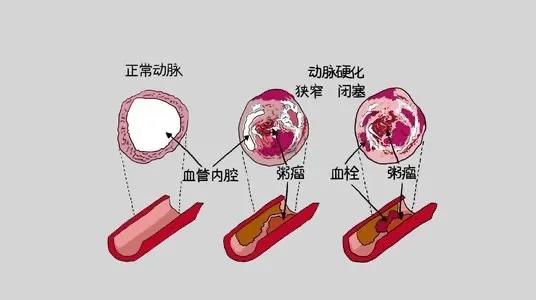

肾移植术后可能引起多种并发症,本期主要关注心血管系统并发症——冠心病。什么是冠心病?冠状动脉粥样硬化性心脏病是指由于冠状动脉粥样硬化使管腔狭窄、痉挛或阻塞导致心肌...

前几天,又一位在抗癌路上坚持了很久的病友因为心梗离世了。她扛过了手术,扛过了化疗,却没扛过不知何时潜伏在她体内的另一个致命物——心血管疾病。有临床数据显示,在恶性...